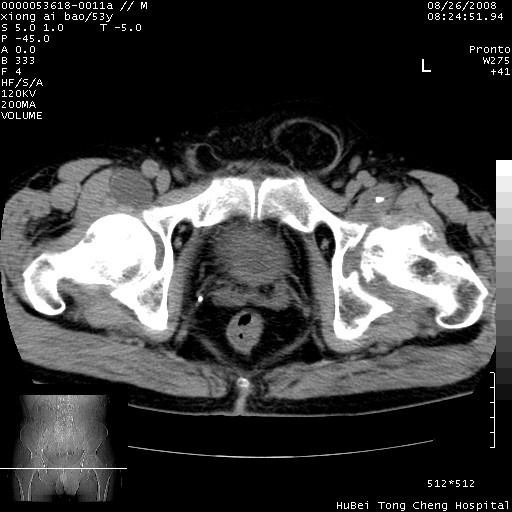

标题: CT15583:M,53Y。请老师指教分析骨盆及其他病变。 [打印本页]

标题: CT15583:M,53Y。请老师指教分析骨盆及其他病变。

双侧股骨头无菌坏死,左侧腹股沟斜疝。

非常典型病例,双侧股骨头坏死伴双髋关节周围软组织肿胀,左腹股沟疝。

双侧股骨头坏死伴双髋关节周围软组织肿胀,左腹股沟疝。

双侧髋关节肿胀明显,感觉还不能排除结核。

考虑双侧髋关节结核,左侧腹股沟疝